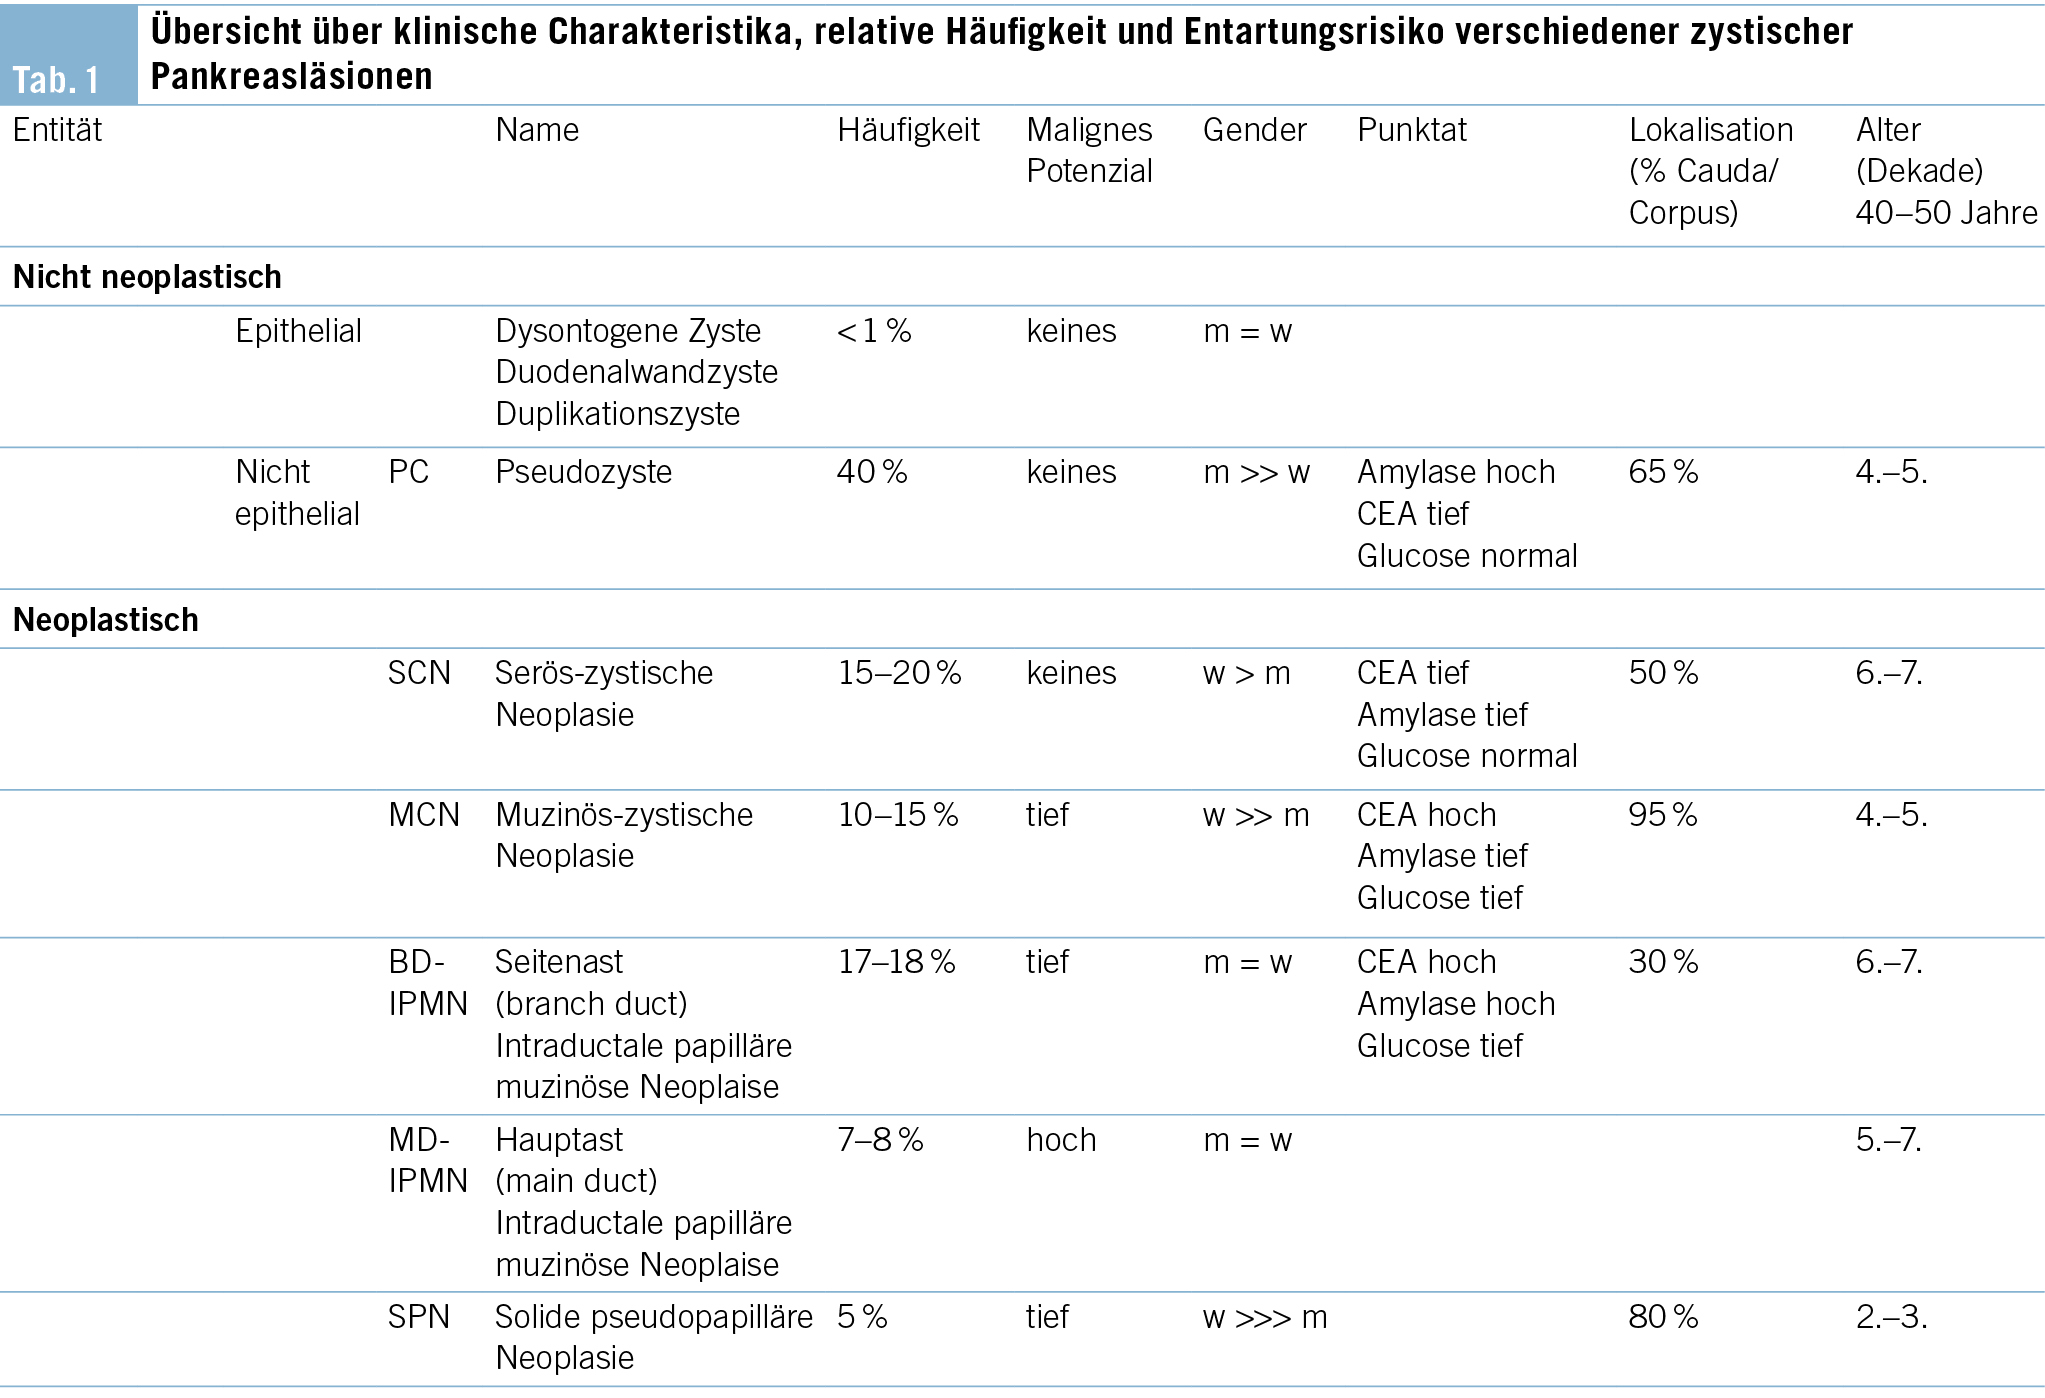

Aus klinischer Sicht stellt sich zunächst die Frage, wie hoch das maligne Potenzial der inzidentell nachgewiesenen zystischen Pankreasläsion zu beziffern ist. Während nicht neoplastische Entitäten wie Pseudozysten oder dysontogene Zysten keinerlei malignes Potenzial aufweisen, handelt es sich bei der Mehrheit der zufällig nachgewiesenen zystischen Pankreasläsionen um neoplastische Zysten respektive Präkanzerosen (Tab. 1). Dementsprechend steht in unserem Beispiel differenzialdiagnostisch eine neoplastische Zyste im Vordergrund, weshalb als nächster Schritt ein MRI durchgeführt wird (Abb. 1a/b), welches eine Verbindung der Läsion zum Gangsystem nachweist. Infolgedessen besteht der dringende Verdacht auf eine Seitenast-IPMN. Aufgrund der Grösse des Befundes entscheidet man sich ferner zur Durchführung einer oberen Endosonographie inkl. Kontrastmittelgabe, wo Noduli definitiv ausgeschlossen werden können (Abb. 1b). Die Analyse der endosonographisch gesteuerten punktierten Zystenflüssigkeit (hohes CEA, hohe Amylase, tiefe Glucose) lässt die Diagnose einer Seitenast-IPMN definitiv stellen. Aufgrund des erhöhten Risikos für die Entwicklung eines Pankreaskarzinoms wird die Aufnahme in ein Surveillance-Programm empfohlen.

Bei der Seitenast-IPMN handelt es sich mit ca. 80 % aller zufällig nachgewiesener zystischer Pankreasneoplasien um die häufigste Entität (2). Das maligne Potenzial hängt von verschiedenen Parametern ab. Wichtigste Kriterien diesbezüglich stellen die Grösse der Läsion, Dilatation des Hauptganges sowie Noduli dar. Hierauf basierend erfolgt eine Risikostratifikation, welche für die weitere Beratung der Patientinnen und Patienten essenziell ist. Diesbezüglich stellt die Arbeit von Mukewar et al. (3) die Verhältnisse sehr anschaulich dar. Während das Risiko eines Pankreaskarzinoms bei einer IPMN mit Hauptgangbeteiligung oder Nodulus als hoch zu bezeichnen ist (ca. 25 %/10 Jahre), ist das Risiko für Patienten mit Seitenast-IPMNs ohne weiterer radiologischer oder klinischer Risikofaktoren deutlich kleiner, relativ zur Normalbevölkerung jedoch immer noch deutlich erhöht (ca. 8 %/ 10 Jahre) (4), wobei das Risiko über die Jahre kontinuierlich ansteigt. Aufgrund der daraus abzuleitenden Indikation zur langfristigen Überwachung ist eine zweifelsfreie Diagnose essenziell. Insbesondere gutartige seröse Zystadenome (Abb. 1c/d) oder inzidentell nachgewiesene Pseudozysten müssen bildgeberisch oder ggf. auch mithilfe einer endosonographisch gesteuerten Punktion ausgeschlossen werden, damit unnötige, repetitive Verlaufskontrollen verhindert werden.

Wichtigste bildgebende Modalität zur Abklärung von zystischen Pankreasläsionen ist das MRI mittels umfassendem multiparametrischem Pankreasprotokoll. In diesem Zusammenhang hat sich die Magnetresonanz-Cholangiopankreatikographie (MRCP) als Standard etabliert, welche eine stark T2-gewichtete Sequenz verwendet. Strukturen mit hohem Wassergehalt stellen sich im Gegensatz zu den umgebenden Weichteilstrukturen hyperintens, d. h. hell, dar, während die umgebenden Weichteilstrukturen dunkel bleiben. Dies führt zum gewollten Aspekt der hellen Darstellung des Pankreasganges, der Gallengänge und auch der zystischen Pankreasläsionen auf dunklem Hintergrund (Abb. 1a).

Im Folgenden sollen die typischen bildgebenden Eigenschaften der häufigsten zystischen Pankreasneoplasien (Tab. 1) beschrieben werden. Die bereits oben erwähnte intraduktale papilläre muzinöse Neoplasie (IPMN) kann sich in drei verschiedenen Formen manifestieren, als Seitengang-, als Hauptgang-IPMN oder als gemischte Form. Sie stellt sich als zystische (T2-hyperintense) Dilatation der besagten Gänge dar, d. h. bei Befall der Seitengänge als uni- oder mulitlokuläre, lobulierte, traubenartige Läsion, bei Befall des Hauptgangs in Form als segmentale oder diffuse Dilatation des Pankreashauptganges ≥ 5mm. Ein spezifisches bildgebendes Kriterium, das die IPMN von den anderen zystischen Neoplasien unterscheidet, ist die nachweisliche Verbindung zum Gangsystem (Abb. 1a). Eine typische Eigenschaft der Seitengang-IPMN ist ausserdem die Multiplizität.

Die serös-zystische Neoplasie (SCN) (Abb. 1c/d) kann sich in Form verschiedener Phänotypen manifestieren. Der typische Aspekt ist allerdings der mikrozystische (Zysten < 2 cm) oder Honigwaben-Aspekt. Die Zysten sind oft so klein, dass in der CT der Eindruck einer soliden Läsion entsteht. Ausserdem typisch ist eine zentrale, manchmal verkalkte Narbe, welche sich computertomographisch bestätigen lässt. Erschwerend kommen in ca. 10 % auch atypische, rein makrozystische Formen der SCN vor, welche bildgebend nicht von einer muzinösen Läsion mit Malignitätspotenzial unterschieden werden können.